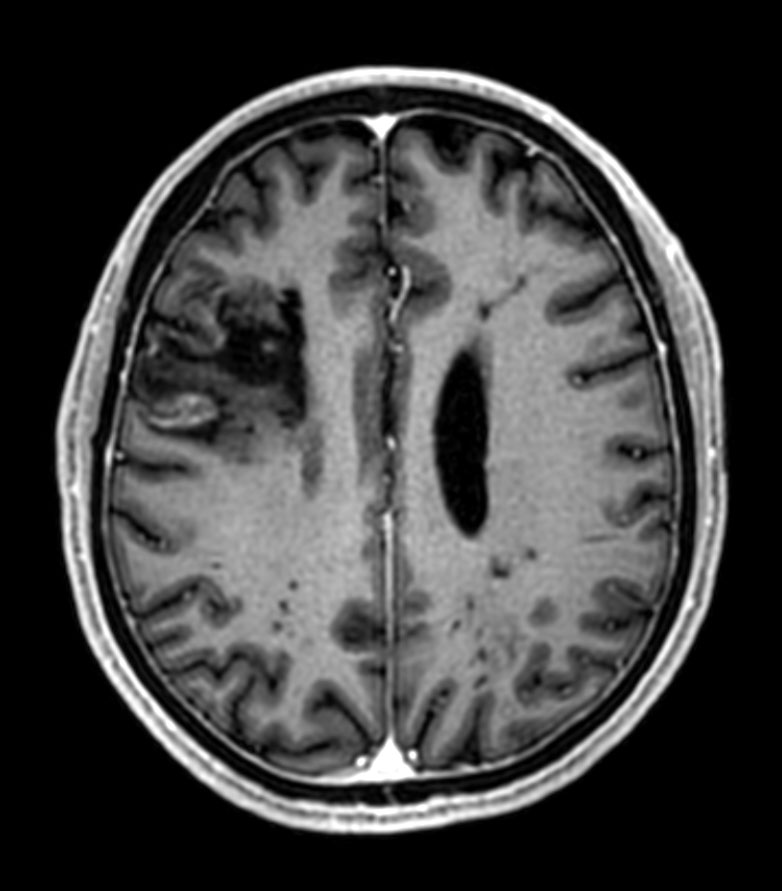

Patient with multiple brain lesions. The ExamCard includes Compressed SENSE to accelerate the entire exam and techniques for motion reduced imaging (MultiVane XD), 3D imaging to acquire high resolution data in multiple directions, 3D susceptibility weighted imaging (SWIp), DWI with EPIC Brain to bring down any residual distortion and Computed DWI to generate synthetic high b-value images.

3D T1w mDIXON XD Compressed SENSE

3D T1w mDIXON XD (reformat) Compressed SENSE